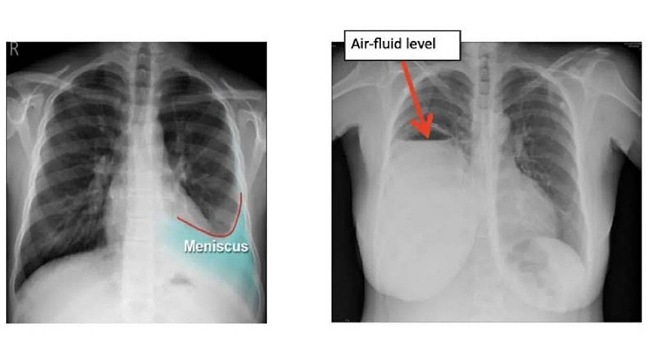

ในกลุ่มที่สองเกิดจากตัวปอดเอง (Exudative Pleural Effusion) ซึ่งมักจะเกิดจากมะเร็ง (เช่น มะเร็งปอด, มะเร็งเต้านมกระจายมาที่เยื่อหุ้มปอด), วัณโรคปอด (Tuberculosis), ปอดติดเชื้อ (Pneumonia) อันเกิดจากเยื่อหุ้มปอดอักเสบหรือมีการอุดตันของระบบน้ำเหลือง รวมถึงของเหลวที่มีโปรตีนสูงและเซลล์อักเสบจำนวนมาก โดยการรักษานั้น หากเกิดจากมะเร็งเราสามารถเอาน้ำออกแล้วใส่ยาเคลือบปอดเพื่อป้องกันการกลับมาเป็นซ้ำได้ (chemical pleurodesis) และในส่วนของกลุ่มที่เกิดภาวะติดเชื้อ เช่น วัณโรคหรือปอดติดเชื้อ หากดำเนินการรักษาแก้อาการของตัวโรค โดยลดอาการบวมน้ำลง อาการก็มักจะดีขึ้นตามมา แต่อาการที่พบในผู้ป่วยอยู่บ่อยครั้ง เช่น มีอาการหายใจลำบาก, มีภาวะเจ็บหน้าอก (โดยเฉพาะเวลาหายใจลึก ๆ) หรือไอแห้ง ๆ มีน้ำเสียงลดลง เหล่านี้แพทย์มักจะวินิจฉัยว่าเกิดจากน้ำในเยื่อหุ้มปอด ซึ่งสามารถใช้การเอกซเรย์ทรวงอก, อัลตราซาวด์ หรือ CT scan และอาจมีการเจาะน้ำในเยื่อหุ้มปอด เพื่อนำไปตรวจหาสาเหตุที่แน่นอน ทั้งนี้การวินิจฉัยน้ำในเยื่อหุ้มปอดนั้น สามารถนำหลักการรักษาน้ำในเยื่อหุ้มปอดให้เป็นปกติได้โดย 1.รักษาตามสาเหตุที่ทำให้เกิดน้ำที่ทำให้เกิดภาวะหัวใจวาย(CHF) โดยส่วนใหญ่จะให้ยาขับปัสสาวะเพื่อลดน้ำในร่างกาย แต่หากผู้ป่วยเป็นวัณโรค ก็จะให้ยาต้านวัณโรคครบสูตร 6-9 เดือน ส่วนผู้ป่วยที่ป่วยเป็นโรคมะเร็ง แพทย์ผู้รักษาจะพิจารณาให้เคมีบำบัด ทำการระบายของเหลวร่วมกับใส่สารเคลือบเยื่อหุ้มปอด(Pleurodesis) เพื่อป้องกันการกลับมาเป็นซ้ำ ส่วนอีกอาการหนึ่งคือ หากเกิดอาการติดเชื้อ เช่น เกิดภาวะปอดบวม แพทย์ผู้ทำการรักษาจะให้ยาปฏิชีวนะร่วมด้วย